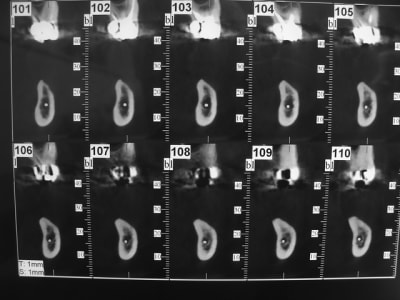

coupe_secteur_3_akuiru.jpg

coupe_sect_4_c0hkw3.jpg